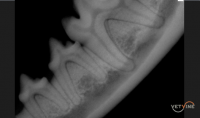

- Normal vs pathologic appearance of the teeth and surrounding structures

- Case examples of various pathologies including periodontal disease, endodontic disease, malformations, oral neoplasia